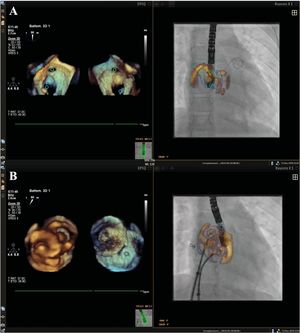

- Evaluación mediante ecocardiografía tridimensional de la geometría del anillo tricuspídeo en niños con cardiopatías congénitas

- Ramona Ghenghea, Clement Karsenty, Pierrick Pyra, Aitor Guitarte, Yves Dulac, Paul Vignaud, Philippe Acar, Khaled Hadeed

- Rev Esp Cardiol. 2026;79:59-67